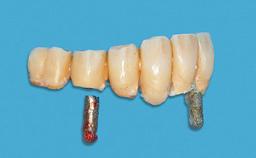

After flapless tooth extraction and a healing period of 6 weeks, a standard-diameter one-piece implant is placed. A gap between the implant and the facial bone wall is filled with autogenous bone chips harvested from the anterior nasal spine and covered with DBBM particles. Contour augmentation on the facial aspect is achieved using DBBM particles and a collagen membrane, according to the principles of guided bone regeneration (GBR). The flap is coronally repositioned for semisubmerged healing.